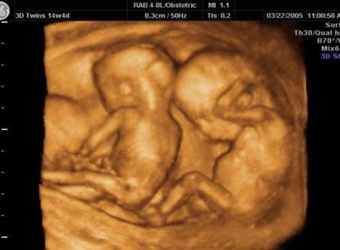

孕期里最重要的检查就是B超检查了,说起四维彩超的好处那真的是数不胜数。下面,就让我们一起通过以下的,【双胞胎四维彩超图片】来进行了解,文中还会告诉你…

四维彩超它是目前最先进的彩超设备,说起四维彩超的功能和作用,相信只要是怀孕过的妈妈们一定都十分清楚,四维彩超不仅可以检测筛查胎儿畸形,而且它还可以很…